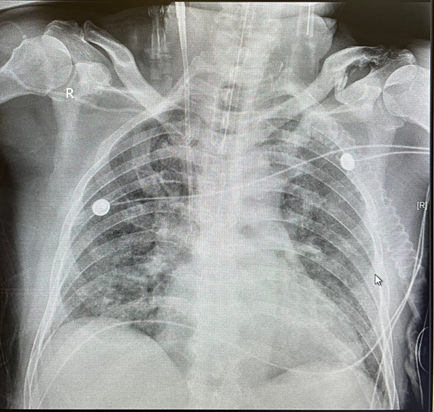

患者于2020年7月28日开始出现胸闷、气促,考虑因腰椎病绑腹带所致,故未予以重视。于8月1日再次出现胸闷、气促加重,并伴咳嗽、痰中带血,无发热;晨起自行骑车于当地医院门诊就诊。胸部CT示:两肺炎症?肺水肿?心影增大(图1)。查血:WBC 9×109/L,N% 90.5%,PLT 47×109/L,Hb 121 g/L,CRP 268 mg/L;心功能标志物:BNP 835 pg/ml;尿常规:尿蛋白(++),尿隐血(+++),白细胞(++),胆红素(++)。

图1 患者门诊胸部CT